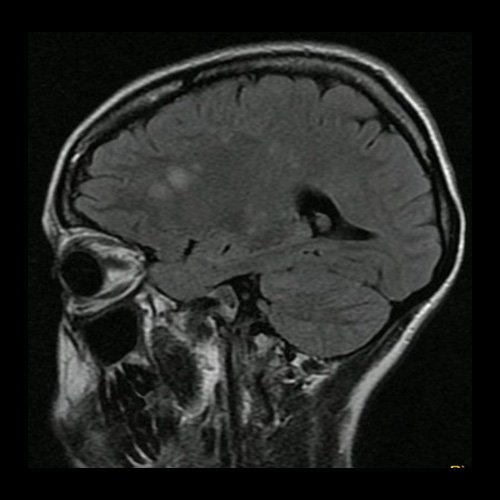

Día 2: RMI de cráneo (T2 Flair-corte axial). Lesiones hiperintensas nodulares sólidas en sustancia blanca en centros semiovales y cuerpo calloso.

Día 2: RMI de cráneo (difusión – corte axial). Lesiones nodulares sólidas en sustancia blanca en centros semiovales y cuerpo calloso con restricción en difusión.

Día 2: RMI de cráneo ( T2 Flair – corte parasagital). Lesiones hiperintensas nodulares sólidas en cuerpo calloso en protuberancia.centros semiovales y cuerpo calloso con restricción en difusión.

Día 2: RMI de cráneo ( T2 Flair – corte axial). Lesiones hiperintensas nodulares sólidas en protuberancia, pedúnculos cerebelosos y hemisferios cerebelosos.

Día 5: RMI de cráneo (T2 Flair – corte parasagital). Lesiones hiperintensas nodulares sólidas en región frontal.